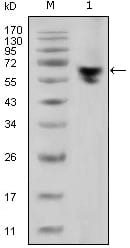

分类: 科研抗体货号: 20338别名: LFS1, TRP53, TP53应用: WB,IHC反应种属: Human